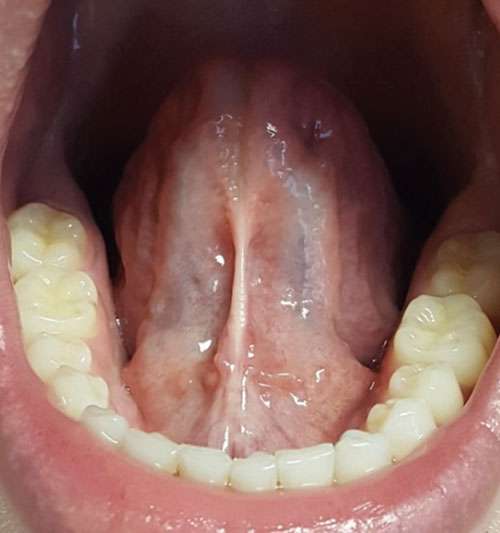

22-year-old healthy male presented for consideration of a revision of a healed lingual frenum (Figures 1A-1B) released 1.5 years prior with a 940 nm diode hot tip (Biolase®, Irvine, CA). He did not do OMT exercises post-release and his tongue felt tight again. He experienced headaches, bilateral TMJ tenderness, pain and tightness in his neck and between the shoulder blades. The patient reported a history of sleep issues. His symptoms included excessive daytime sleepiness and fatigue, low energy, moodiness, and restlessness. He had no history of drug or alcohol use and was currently taking no medications. The patient had a sleep study performed (WatchPat Home Device) and was diagnosed with a sleep disorder.

Patient had had routine dental hygiene care and required no restorative dentistry. Moderate occlusal wear revealed a history of bruxism, and non-extraction orthodontic therapy involving maxillary palatal expansion and mandibular advancement with a fixed Herbst appliance was also reported. Prior to his diode frenectomy, the patient presented with bilateral TMJ tenderness, asymptomatic bilateral subluxation of the condyles, lateral excursions of 10 mm bilaterally with poor lingual-mandibular differentiation. No nasal deviation was noted, nasal airway was patent. The intraoral exam revealed a restricted lingual frenulum after the previous frenectomy was completed with a 940 nm diode hot tip. There was a decrease in the elevation of the tongue and tongue-to-spot (TTS) placement. At the time of his appointment for the second frenectomy, the patient’s Mallampati score was 2.